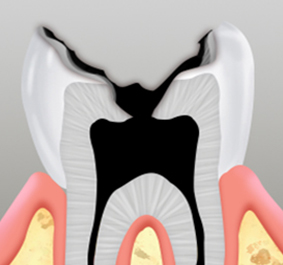

신경조직과 뿌리

끝까지 진행된 상태

치아의 손상 정도가 심각하여 치아 내부 조직인 신경 혈관에 염증이 생긴 경우,

내부 조직을 제거한 후 치과용 충전재료를 충전한 후 크라운을 씌워 마감합니다.